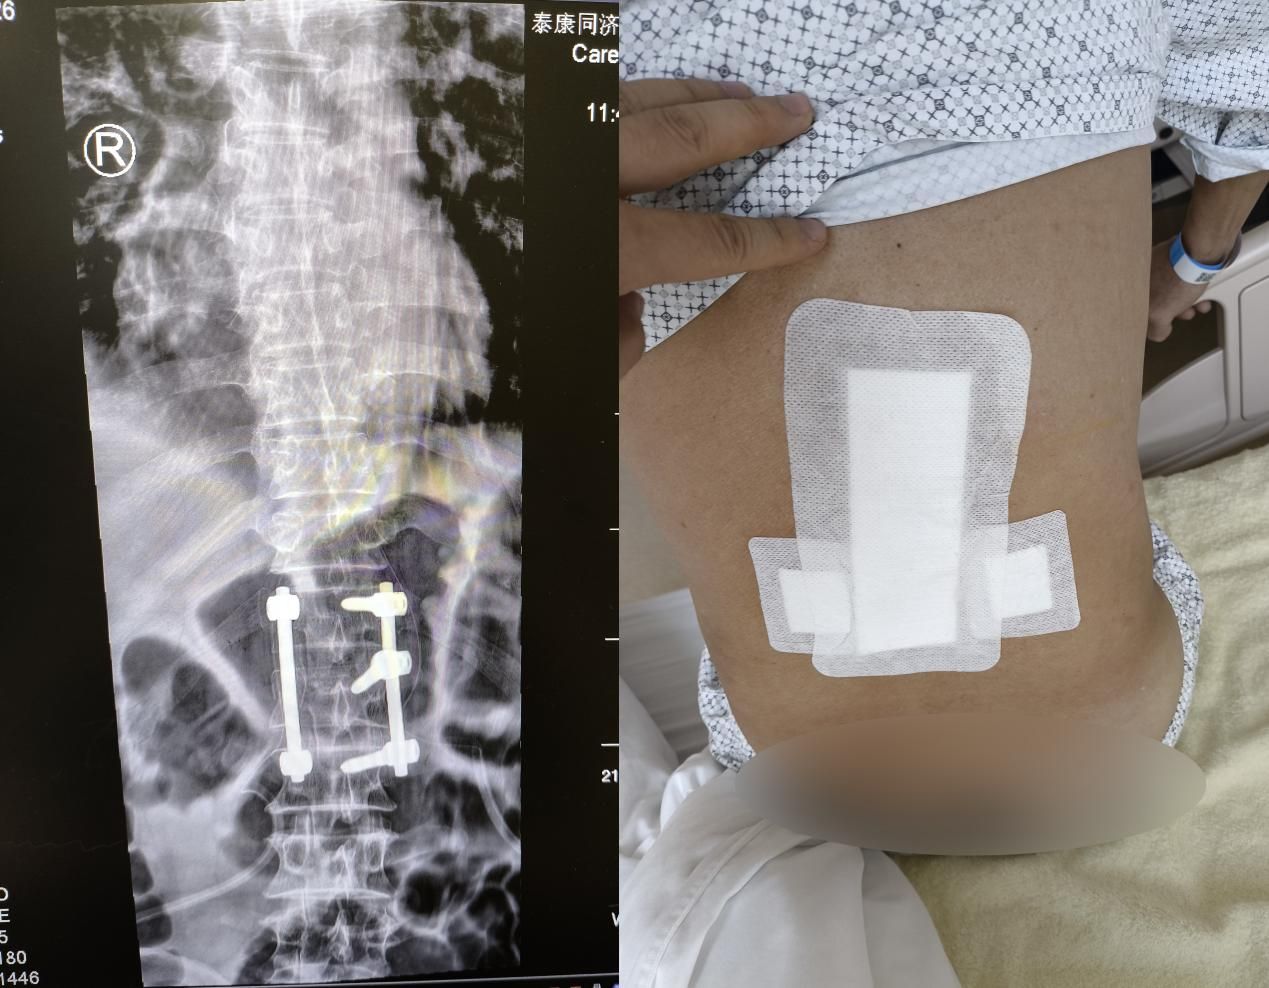

近日,泰康同济(武汉)医院创伤外科团队成功为高处坠落致腰椎严重骨折的男性患者实施“肌间隙微创入路腰椎骨折切开复位内固定术”,手术以极小创伤重建患者脊柱稳定性,让身为家庭“顶梁柱”的患者重拾生活信心,即将回归正常工作与生活。

在经过与患者的充分沟通后,10月17日,由张俊主任领衔的手术团队正式为王先生实施手术。术中,张俊和冯琼华医生凭借精准的解剖定位、娴熟的微创操作技巧,通过微小切口,在影像引导下精准置入内固定物,成功完成骨折椎体的复位与固定,整个手术过程流畅有序。

“传统开放手术治疗此类骨折,出血量通常在数百毫升,而这次微创手术出血量仅约70毫升,不足传统手术的五分之一。”主刀医生张俊主任介绍,肌间隙入路的核心优势在于不破坏脊柱后柱结构,手术入路是经由天然肌肉间隙进入,无需大面积剥离和切断腰背肌群,这不仅能有效维持术后脊柱长期稳定性,更让患者术后超早期康复锻炼成为可能,从根本上缩短了恢复周期。

得益于微创手术的独特优势,王先生的恢复情况远超预期:术后第3-4天,即可在支具保护下自主坐起,腰部疼痛明显缓解;术后仅一周,便能脱离卧床状态,在康复师和护士的指导下下地缓慢行走;目前,王先生已进入系统功能康复阶段,腰部活动度逐步恢复,精神状态日渐饱满。